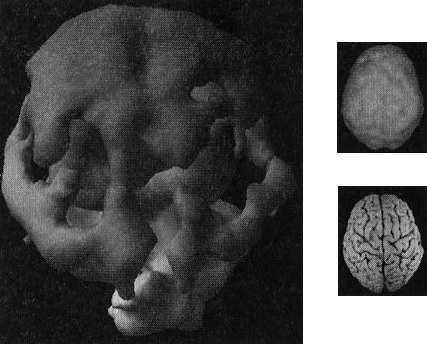

Наконец, рис. Г показывает трехмерную картину активности здорового мозга, вид снизу, а под ней находится иконка с моделью мозга в той же проекции. ![]() Помните, что трехмерные поверхностные сканы помогают увидеть малоактивные области, а трехмерные функциональные сканы помогают обнаружить гиперактивные области. Как не бывает двух одинаковых лиц, так нельзя встретить и два одинаково выглядящих мозга. С эстетической точки зрения бывают красивые и уродливые, банальные и причудливые мозги. Но всегда справедливо — и это доказали 30 000 проведенных мною сканирований, — что активность здорового мозга должна быть достаточной, полной, равномерной и симметричной. В здоровом мозге целы все важные участки, и все они работают гармонично. Возрастные вариации нормальны. Сканы мозга детей и подростков показывают большую активность, чем у взрослых. Но даже у пожилых людей мозг будет здоровым, если о нем заботились в течение жизни. Давайте взглянем на несколько примеров здорового и не очень здорового мозга. Однажды я предложил студентам стать добровольцами в исследовании функционирования мозга. Кристи, одна из вызвавшихся, воскликнула: «Вам обязательно нужно проверить мою бабушку Анну. Ей 82 года, но среди всех, кого я знаю, она одна из самых нормальных. Она вам понравится!» Бабушка согласилась, и мы провели томографию. Действительно, обнаружилось, что мозг этой пожилой женщины здоров, а ее жизнь соответствует всем критериям профилактики здоровья мозга (она не употребляла наркотики, не получала травм головы, не имела родственников первой степени с психиатрическими заболеваниями и т. д.). В течение 58 лет Анна была замужем, всегда оставаясь любящей женой, матерью и бабушкой, ее ум был острым и деятельным. Кроме того, она активно участвовала в делах местной церкви и муниципалитета. Она создала прочные и длительные отношения с родными и друзьями. Скан мозга Анны — один из самых здоровых в моей базе данных (рис. 2.5 и 2.6). Скан здорового мозга Анны, 82 года Рис. 2.5 Вид сверху Полная симметричная активность ![]() Рис. 2.6 Вид снизу Полная симметричная активность ![]() Двадцатилетний Брюс, несмотря на молодость, годами злоупотреблял наркотиками: героином, марихуаной, амфетаминами, галлюциногенами, экстази и обезболивающими. Я познакомился с ним, когда снимал образовательный фильм о вреде наркотиков. Брюс не был способен завязать со своим пристрастием. Отношения с родными разладились. Он стыдился себя и своего поведения. Как вы сами можете увидеть, мозг 82-летней Анны на томограмме выглядит значительно здоровее поврежденного наркотиками мозга молодого Брюса (рис. 2.7). Поврежденный наркотиками мозг Брюса Рис. 2.7 Вид сверху Значительные повреждения ![]() В норме с возрастом мозг становится все менее активным, поэтому если очень пожилая женщина обладает значительно более здоровым мозгом, чем 20-летний парень, значит, у этого парня серьезные неприятности. Я убедился, что люди со здоровым мозгом ведут себя эффективно и всегда движутся к поставленным целям. Они прекрасные сотрудники, супруги, родители, друзья и граждане. Люди же с поврежденным мозгом с трудом бредут по жизни. Вспомните про болезнь Альцгеймера (БА): можно ли сказать, что заболевшие ею способны полноценно проявлять свою волю и личность? Вероятно, нет. У людей с БА функционал мозга значительно поврежден. От этой болезни страдала мать моей подруги Айзы Гиббонс, основавшей ряд центров поддержки для людей с БА и членов их семей. Мать Лизы из доброй, мягкой женщины превратилась в озлобленного, иррационального и агрессивного человека (рис. 2.8). Мозг пациента с болезнью Альцгеймера Рис. 2.8 Вид сверху Значительно снижена активность в задних частях мозга ![]() Гиперактивность мозга часто связана с обсессивно-компульсивным [2] и биполярным расстройствами и другими заболеваниями. 17-летняя Хитер очень много пила и не ладила с семьей. Я сделал томографию мозга ей и ее брату для телепередачи «Правда о выпивке», которая позже получила премию «Эмми». На сканах вы видите области очень высокой активности (рис. 2.9). Неудивительно, что девушка начала пить — она пыталась успокоить свой мозг. Гиперактивный мозг Хитер Рис. 2.9 Вид функциональной активности снизу Значительно снижена общая активность ![]() 45-летний Джимми обратился ко мне с посттравматическим стрессовым расстройством, вызванным пожаром. Томограмма показала множественные области повышенной активности, о которых можно было догадаться, судя по его тревожности, депрессии и страхам. Эмоциональные центры его мозга работали чересчур напряженно, и моей задачей было их успокоить (рис. 2.10). Гиперактивный мозг Джимми Рис. 2.10 Вид функциональной активности снизу Повышенная активность в глубоких областях мозга ![]() А теперь вернемся к разнице между «волевым» и «мозговым поведением». Плохо работающий мозг лишает людей силы воли и провоцирует деструктивные поступки. Люди с обсессивно-компульсивным расстройством (ОКР), синдромом Туретта (СТ) или зависимостью от наркотиков, скорее всего, стали жертвами своего мозга. Для ОКР характерны вызывающие огорчение навязчивые мысли или компульсивное поведение (непрерывная проверка дверных замков, постоянное мытье рук, следование ритуалам). Даже если человек понимает, что его мысли и поступки иррациональны, он все равно не может от них отказаться. В тяжелых случаях такие мысли и действия занимают большую часть дня. Сканы показывают, что при ОКР гиперактивна передняя часть мозга, провоцирующая навязчивые мысли (обсессия) или действия (компульсия). |